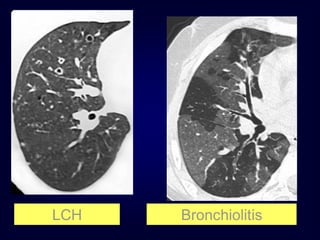

• 104.

Langerhans Cell Histiocytosis HRCTFindings Small peribronchiolar nodules (1-5mm) Thin-walled cysts (< 1cm), Bizarre and confluent Ground glass opacities Late signs: irreversible / parenchymal fibrosis Honey comb lung, septal thickening, bronchiectasis

• 105.

Langerhans Cell Histiocytosis 1year later Peribronchiolar Nodules Cavitating nodules and cysts

• 107.

Langerhans Cell Histiozytosis KeyFeatures Upper lobe predominance Combination of cysts and noduli Characteristic stages Increased Lung volume Sparing of costophrenic angle S M O K I N G

Langerhans Cell Histiocytosis DifferentialDiagnosis Only small nodules Sarcoidosis, Silicosis Only cysts idiopathic Fibrosis LAM Destructive emphysema